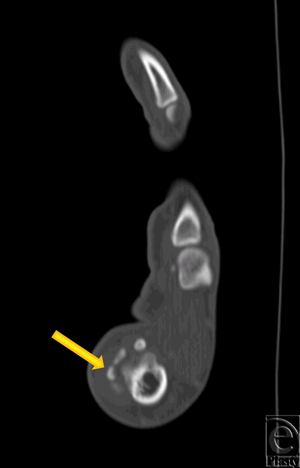

After 24 hours, physical examination revealed moderately decreased erythema and swelling and improvement of thumb ROM. Severe thumb pain persisted. A hand surgery consult was requested, and CT scan of the hand was obtained. Consistent with the initial x-rays, foci of mineralization adjacent to the thumb MP joint were noted (Fig 2). This was again suggestive of synovial chondromatosis. The thumb was placed in a spica splint and the patient was seen in hand clinic the following week. After 1 week of immobilization, swelling of the thumb had subsided but pain and tenderness at the first MP joint persisted. Total active motion of the thumb was 36°. Surgical excision of the masses identified by radiography was subsequently recommended.